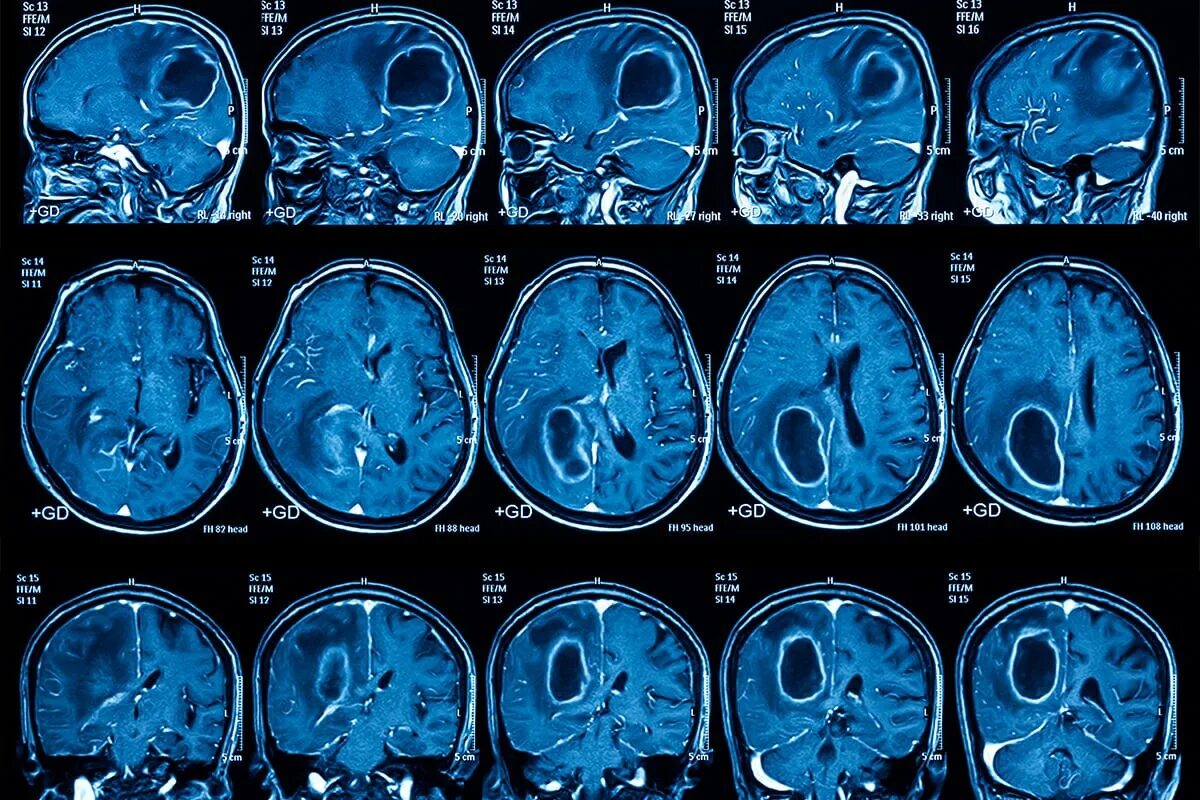

Отек головного мозга мрт